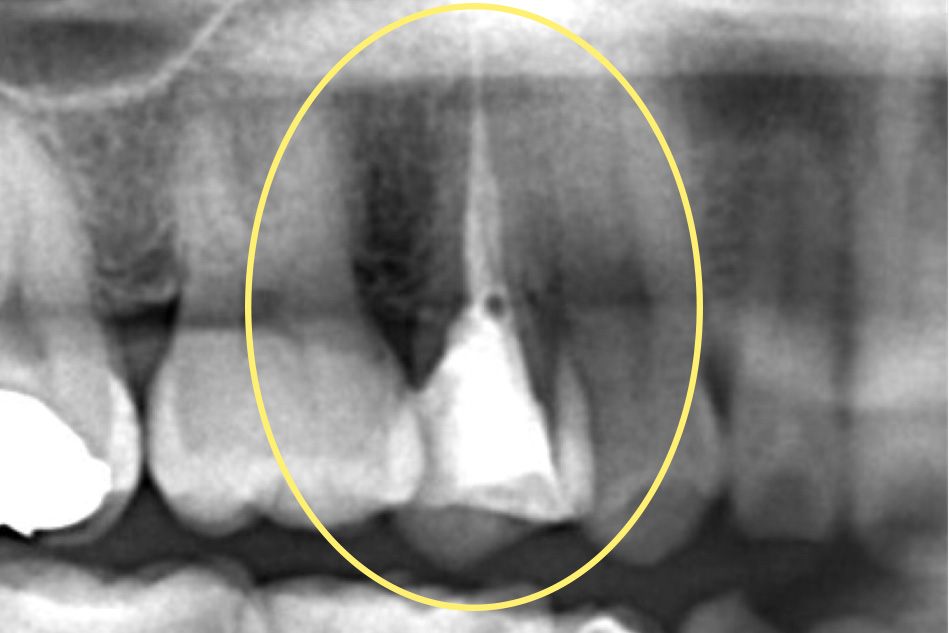

X線画像撮影(デンタルX線画像+歯科用CT画像)

虫歯の深さ・歯の残っている量・根尖部透過像(レントゲンに映る膿の影)の有無と大きさ・根管の数と形

また、一度根管治療を受けたことがある歯は、しばしば誤って歯に穴があいて骨と貫通してしまっている場合があります。穴のあいた部分のまわりの骨は炎症を起こし、骨が溶けてしまいます。必要に応じて穴を、生体親和性にすぐれたMTAセメントやバイオセラミックで充填します。穴を緊密に封鎖することで、炎症が治り、骨が再生します。とても繊細な技術が必要になります。これによって、今までは抜歯と言われていた穴のあいた歯も、条件によっては残せるようになりました。